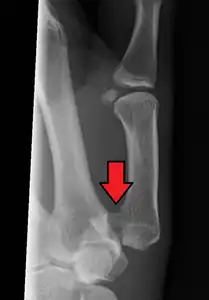

- In the most minor cases of Bennett fracture, there may be only small avulsion fractures, relatively little joint instability, and minimal subluxation of the CMC joint (less than 1 mm). In such cases, closed reduction followed by immobilization in a thumb spica cast and serial radiography may be all that is required for effective treatment.[8]

- For Bennett fractures where there is between 1 mm and 3 mm of displacement at the trapeziometacarpal joint, closed reduction and percutaneous pin fixation (CRPP) with Kirschner wires is often sufficient to ensure a satisfactory functional outcome. The wires are not employed to connect the two fracture fragments together, but rather to secure the first or second metacarpal to the trapezium.

- For Bennett fractures where there is more than 3 mm of displacement at the trapeziometacarpal joint, open reduction and internal fixation (ORIF) is typically recommended.

Regardless of which approach is employed (nonsurgical, CRPP, or ORIF), immobilization in a cast or thumb spica splint is required for four to six weeks.